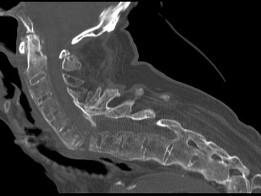

问题 男,92岁,下腰不适伴晨僵半年余,请结合影像学检查,选出最可能的诊断 ( )

选项 A、阻滞椎 B、类风湿关节炎 C、强直性脊柱炎 D、化脓性脊柱炎 E、脊椎退行性变

答案 C